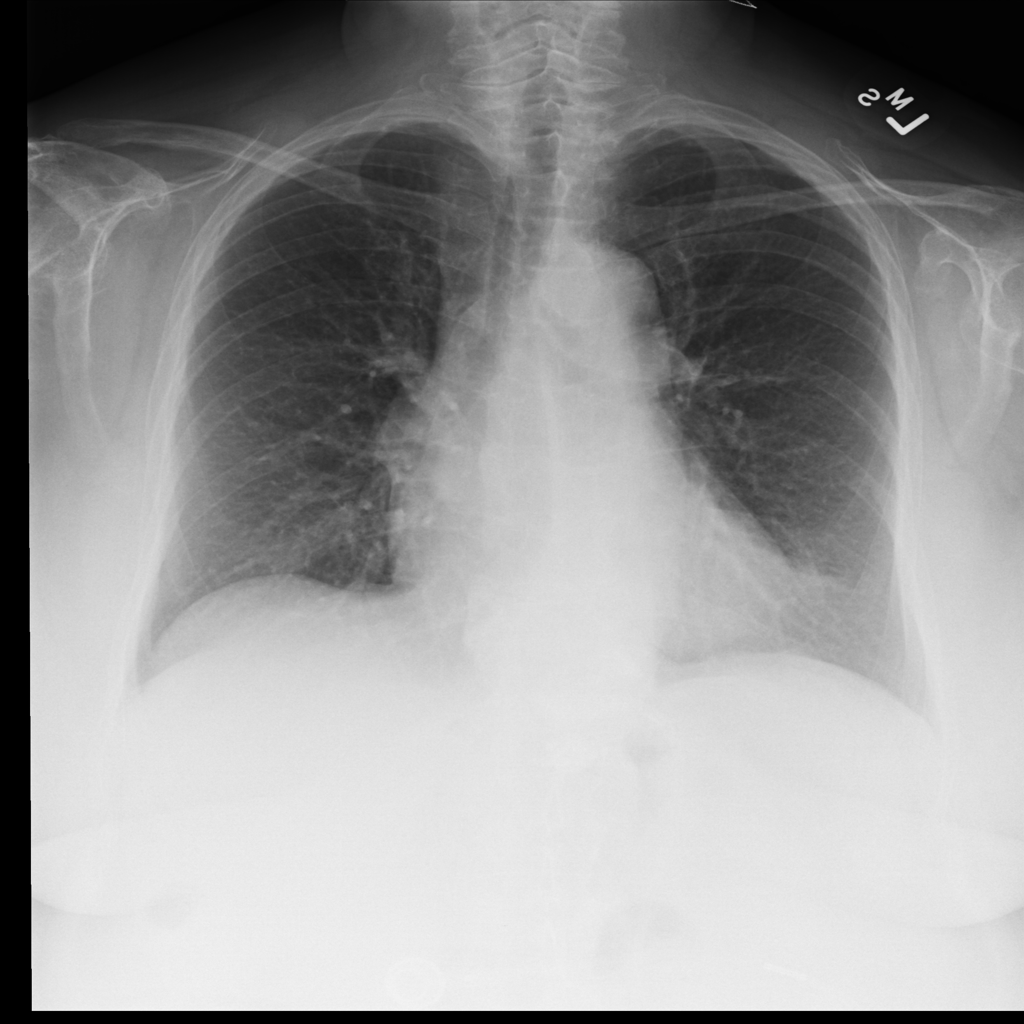

PAT-E828 · IMG-005Edema

PAT-E828 · IMG-005

AP